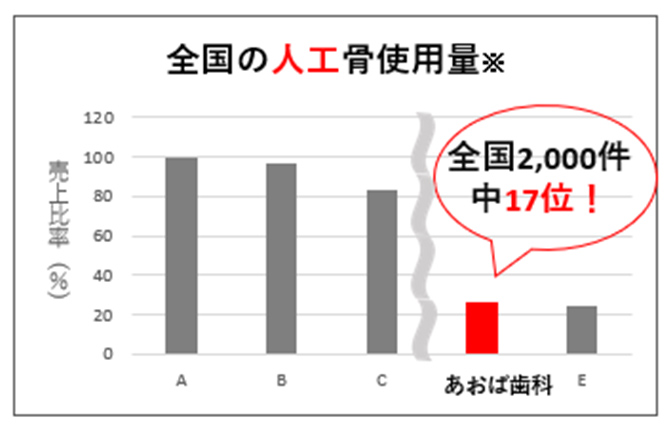

埼玉県内で

昨年も高い

再生医療実績(2025年)

| 前歯 | 小臼歯 | 大臼歯 | 合計 |

|---|---|---|---|

| 1,516本 | 683本 | 1,981本 | 4,180本 |

(歯科歴25年間に行った感染根管治療の本数は、約7,000本です)